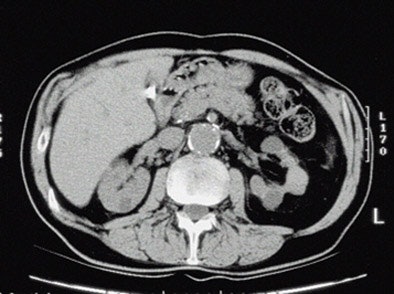

| Top to bottom: Indented kidneys with cysts typical of ESRD, but not 'SICK,' seen in a 61-year-old patient. All patients were imaged within three months of ESRD diagnosis and the beginning of dialysis, and yielded only subtle CT findings in most of them. All images courtesy of Lauren Brubaker. |

"We developed the acronym 'SICK' to indicate bilaterally small, indented, and calcified kidneys," she said. "In terms of radiological findings, as you would expect, we found small, smooth kidneys in 65% of our ESRD population. Other typical ESRD patterns were small kidneys with cysts, as well as kidneys with so many cysts they are causing indentations or scars within the kidneys. Contour was assessed for calcification through scars, as well as calcifications for size and location."